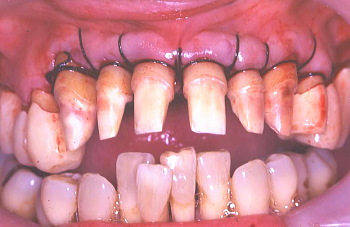

⑥ 骨が異常に減退しているので歯冠が長く見える。また歯の根っこの表面に歯石が見られ、これが存在する限り、歯周病はよくならないのでこれを取り除くのも一つの大きな外科の目的である。○印で示しているのは歯周ポケットの中で歯根面に付着していた歯石である。

⑦ この写真でも骨が異常に減退した長い歯冠とその歯の根っこの表面に歯石が見られる。○印で示しているのは歯周ポケットの中で歯根面に付着している歯石。

⑧ 歯根に付着していた歯石を除去した。もう一つの大きな外科手術の目的は歯周骨が細菌作用により、デコボコになった骨の表面部分を滑らかに整える事である。